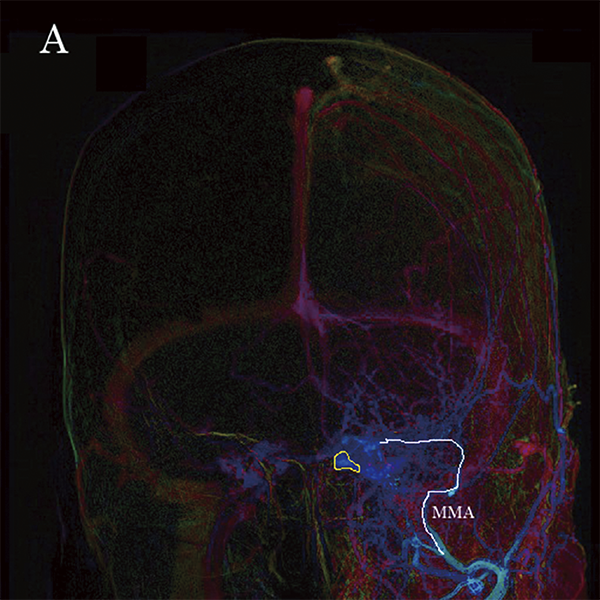

Для вирішення цієї проблеми доступний інструмент підтримки, відомий як Parametric Imaging (PI). PI відображає час надходження контрастної речовини різними кольорами на основі ангіографічних зображень. (малюнок 9A і 9B). Однак при використанні цього інструменту потрібен певний рівень навичок, щоб зрозуміти напрямок кровотоку, оскільки інформація відображається у вигляді статичного зображення.

Малюнок 9A: TTP зображення CSdAVF (вид спереду), отримане за допомогою Parametric imaging (PI).

Малюнок 9B: TTP зображення CSdAVF (бічне зображення), отримане за допомогою Parametric imaging (PI).